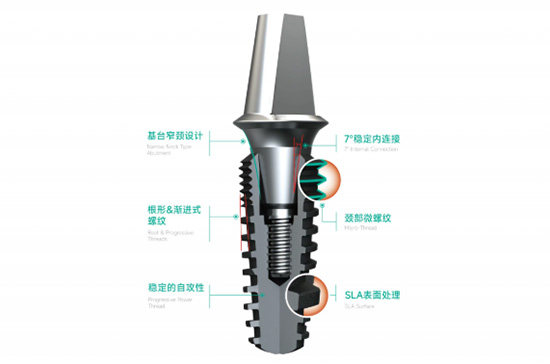

2. 精密的表面处理工艺

沃兰种植体采用了较高的**双重酸蚀处理(SLA)**等表面处理技术。这种工艺能够使种植体表面形成微观的粗糙度和多级孔隙结构,极大地增加了表面积。

加速骨结合: 这种特殊的表面结构能够更好地引导骨细胞的生长和附着,显著缩短种植体与骨组织的融合时间,提高骨结合的可行性。

增强稳定性: 牢固的骨结合是种植体长期稳定的关键。沃兰种植体通过优化的表面处理,为种植体的稳固提供了有力因素。